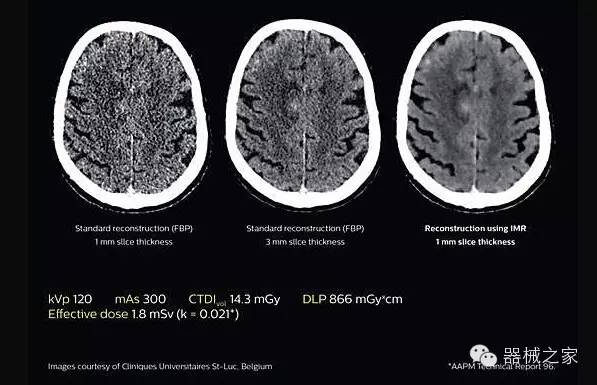

2.腦部顯影

透過數(shù)字化影真芯片DAS系統(tǒng)、球面微平板探測器技術(shù)和濾線柵技術(shù)等硬件技術(shù),整體提高探測器成像的能力,奠定低劑量條件下高清成像的基礎(chǔ);

應(yīng)用目前業(yè)界領(lǐng)先的新一代星光平臺(tái)iDose4 Premium及基于迭代基礎(chǔ)的O一MAR去除金屬偽影技術(shù),達(dá)成微量輻射下零偽影的高清晰成像;